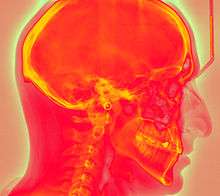

Computed radiography (CR) uses very similar equipment to conventional radiography except that in place of a film to create the image, an imaging plate (IP) made of photostimulable phosphor is used. The imaging plate is housed in a special cassette and placed under the body part or object to be examined and the x-ray exposure is made. Hence, instead of taking an exposed film into a darkroom for developing in chemical tanks or an automatic film processor, the imaging plate is run through a special laser scanner, or CR reader, that reads and digitizes the image. The digital image can then be viewed and enhanced using software that has functions very similar to other conventional digital image-processing software, such as contrast, brightness, filtration and zoom.

The CR imaging plate (IP) contains a photostimulable storage phosphor layer (typically 0.1 to 0.3 mm thick), which stores the radiation dose as a latent image within the phosphor layer as elevated electron energies. When the IP is then transported through the scanner (read out), the scanning laser beam causes the electrons to relax to lower energy levels (photostimulated luminescence), emitting light that is detected by a photo-multiplier tube, which is clocked at a specific resolution or pixel capture frequency, this signal then being converted to an electronic signal and significantly amplified. The electronic signal is then quantized via an ADC to discrete (digital) values for each pixel and placed into the image processor pixel map.